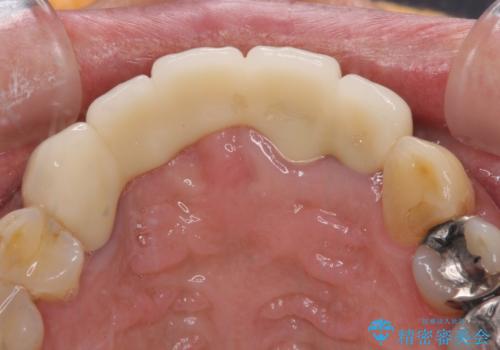

- 前歯のブリッジのせいで話しにくく、金属の縁などが露出して見栄えが悪いので、作り直したいとのことで来院された患者様です。

土台となる歯は根管治療の結果が良好ではないため、根管治療からやり直しをした後、オールセラミックブリッジにて補綴することとしました。

露出していた歯根や金属の縁が見えてしまい、人前で話すときの目線が気になっていらっしゃいましたが、歯肉の位置に縁を合わせてことで自然な仕上がりとなりました。

露出していた歯根が覆われるため、歯冠が長く見えてしまうことが懸念されましたが特に気になることはなく、患者様には大変満足していただきました。